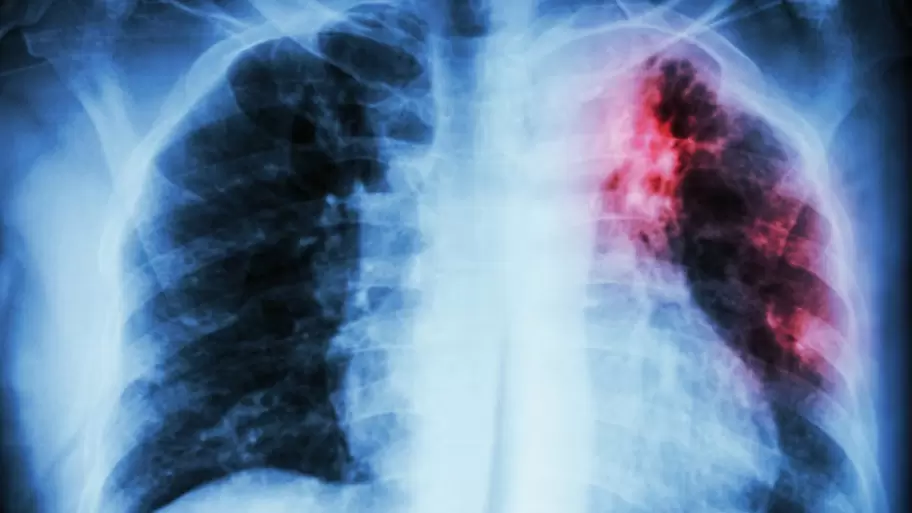

La tuberculosis, una enfermedad bacteriana que suele atacar principalmente los pulmones pero también puede comprometer órganos como los riñones, la columna vertebral o el cerebro, vuelve a convertirse en una amenaza creciente en Argentina. Los gérmenes se propagan a través del aire -al toser, estornudar, hablar o cantar- porque "las personas que tienen enfermedad de tuberculosis en la garganta o los pulmones propagan los gérmenes en el aire". A diferencia de los mitos que resurgen cada vez que los casos aumentan, "esta enfermedad no se contagia al tocar, besar o compartir alimentos o platos".